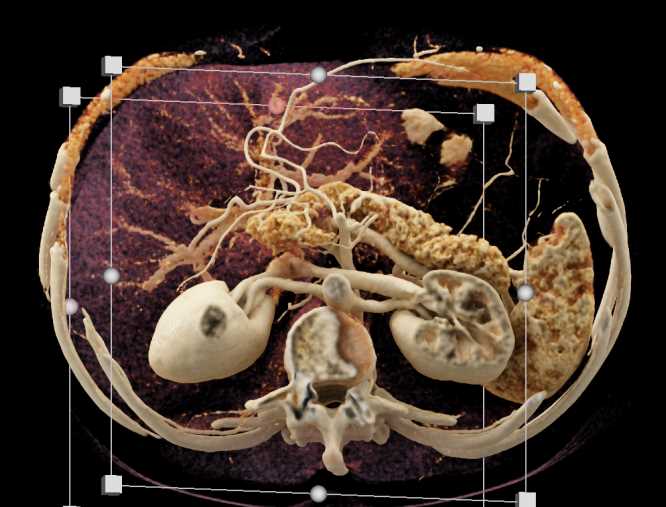

Subtle Neuroendocrine Tumor Body of Pancreas